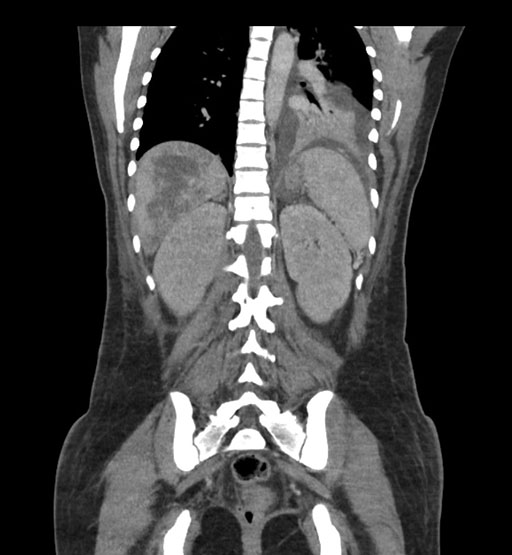

Coronal Venous